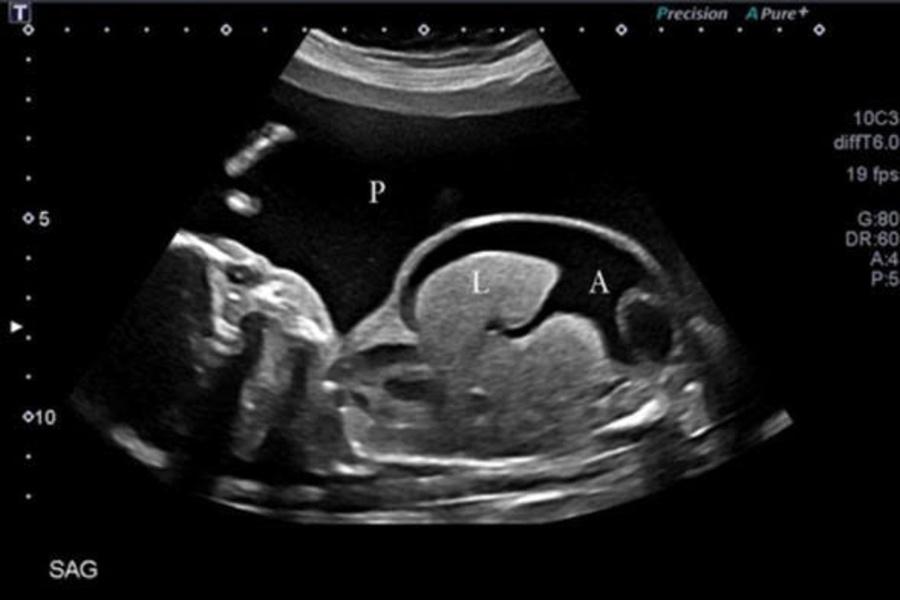

Trong những trường hợp thiếu máu bào thai mức độ nặng, truyền máu cho thai nhi qua dây rốn được xem là phương pháp điều trị tối ưu và hiệu quả nhất hiện nay. Kỹ thuật này cho phép đưa trực tiếp lượng máu đã được lựa chọn, kiểm soát nghiêm ngặt về nhóm máu và chất lượng vào hệ tuần hoàn của thai nhi thông qua tĩnh mạch dây rốn, dưới hướng dẫn của siêu âm.